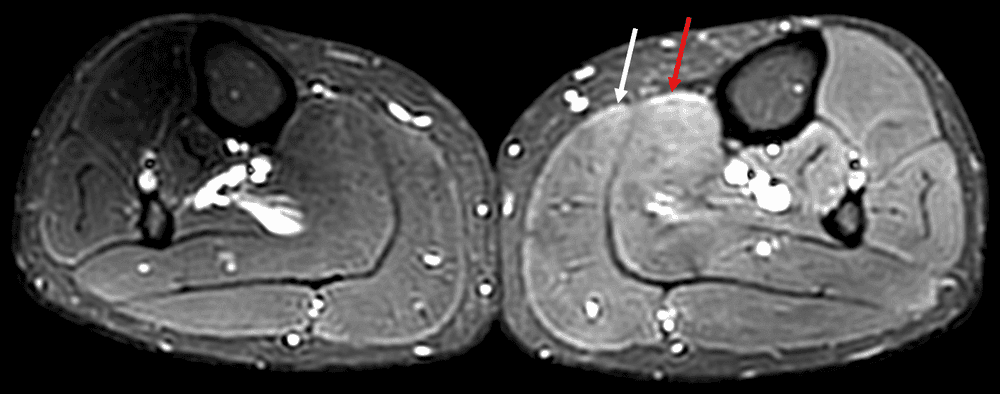

Douleurs musculaires d'apparition retardée - DOMS (Delayed Onset Muscle Soreness)

MRI